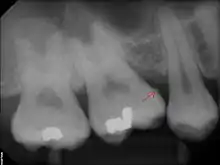

Sub-gingival calculus is composed almost entirely of two components: fossilized anaerobic bacteria whose biological composition has been replaced by calcium phosphate salts, and calcium phosphate salts that have joined the fossilized bacteria in calculus formations.[37][38] The initial attachment mechanism and the development of mature calculus formations are based on electrical charge.[39] Unlike calcium phosphate, the primary component of teeth, calcium phosphate salts exist as electrically unstable ions. The following minerals are detectable in calculus by X-ray diffraction: brushite (CaHPO4 · 2 H2O), octacalcium phosphate (Ca8H2(PO4)6 · 5 H2O), magnesium-containing whitlockite (Ca9(Mg,Fe)(PO4)6(PO3OH)), and carbonate-containing hydroxyapatite (approximately Ca5(PO4)3OH but containing some carbonate).[40]

The reason fossilized bacteria are initially attracted to one part of the subgingival tooth surface over another is not fully understood; once the first layer is attached, ionized calculus components are naturally attracted to the same places due to electrical charge. The fossilized bacteria pile on top of one another, in a rather haphazard manner. All the while, free-floating ionic components fill in the gaps left by the fossilized bacteria. The resultant hardened structure can be compared to concrete; with the fossilized bacteria playing the role of aggregate, and the smaller calcium phosphate salts being the cement. The once purely electrical association of fossilized bacteria then becomes mechanical, with the introduction of free-floating calcium phosphate salts. The "hardened" calculus formations are at the heart of periodontal disease and treatment.[38]